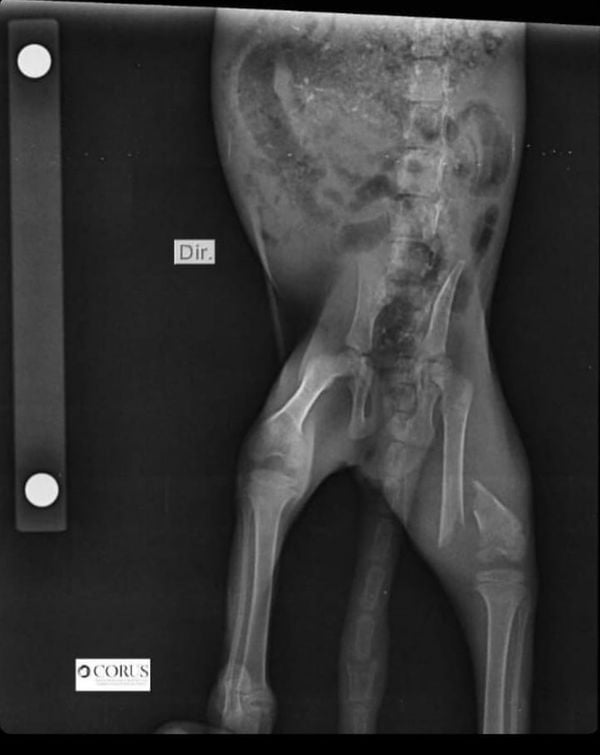

Uma fêmea filhote de gato-maracajá foi resgatada depois de ser atacada por cachorros em Conceição da Barra, no Norte do Estado. O animal, cujo nome científico é Leopardus wiedii e integra a lista de espécies em extinção, teve o fêmur quebrado no ataque e terá de passar por uma cirurgia em Vitória nesta quinta-feira (17), na qual será colocada uma placa de titânio na pata.

O filhote teve o fêmur quebrado por conta do ataque e será operado nesta quinta (17)

O filhote teve o fêmur quebrado por conta do ataque e será operado nesta quinta (17) Crédito: Arquivo Pessoal

Diogo Garnica explicou que a mãe e a filhotinha foram atacadas por cachorros domésticos. A mãe fugiu e o bichinho acabou sendo alvo dos cães. Ela foi resgatada por uma equipe do Instituto de Meio Ambiente e Recursos Hídricos (Iema) Segundo o médico veterinário, trata-se de um procedimento complexo por conta do tamanho do exemplar e da gravidade da lesão.

"É uma cirurgia extremamente complexa pelo tamanho do indivíduo, que tem 600 gramas. E demanda toda uma equipe, tem anestesista, cirurgião auxiliar, instrumentador. Os implantes são de tamanhos especiais, de titânio. Tem que ser implante que tenha ósseo-integração, porque vai ficar ali para o resto da vida dela", disse.

A cirurgia, segundo Diogo Garnica, é complexa por causa do tamanho do animal

A cirurgia, segundo Diogo Garnica, é complexa por causa do tamanho do animal Crédito: Arquivo Pessoal